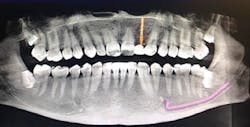

A 32-year-old male presented with a congenitally missing lateral, No. 10. The buccal-lingual dimensions were sufficient for standard implant placement, but the mesial-distal dimensions were 4.56 mm (figures 1a and 1b). The patient had a failing Maryland bridge, both functionally and esthetically (figure 2). He was always told that implants were not an option for him unless he underwent significant orthodontic treatment, and even then, nothing was guaranteed.

Figure 1a: Pre-op panorex

Figure 1b: Pre-op CT scan